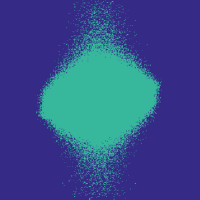

Figure 7 illustrates the best-performing randomized indices vs. our learned set of indices in the -space along the and directions. When optimized for the linear decoder, the indices of [3, 4] concentrate on low frequencies. While our strategies based on optimizing and (again using ) also do this to some extent, there is a stark contrast in the shape, since we do not restrict ourselves to patterns exhibiting circular symmetry.

Table III illustrates the overall test performance of each approach, in addition to the error obtained by the best adaptive (i.e., image dependent) -sample approximations with respect to the -space basis. Based on these numbers, the learning-based approach slightly outperforms the randomized variable-density based approach of Roman et al. [4], which in turn slightly outperforms that of Lustig et al. [3]. The best PSNR in each case is achieved by the indices corresponding to ; with this choice, even the linear decoder leads to an improvement over [3] and [4] used with BP, while using our indices alongside BP provides a further improvement. Finally, based on Figure 8, it appears that the improvement of our indices is actually more significant in the relevant parts of the image where the knee is observed, with finer details being seen at and sampling rates.